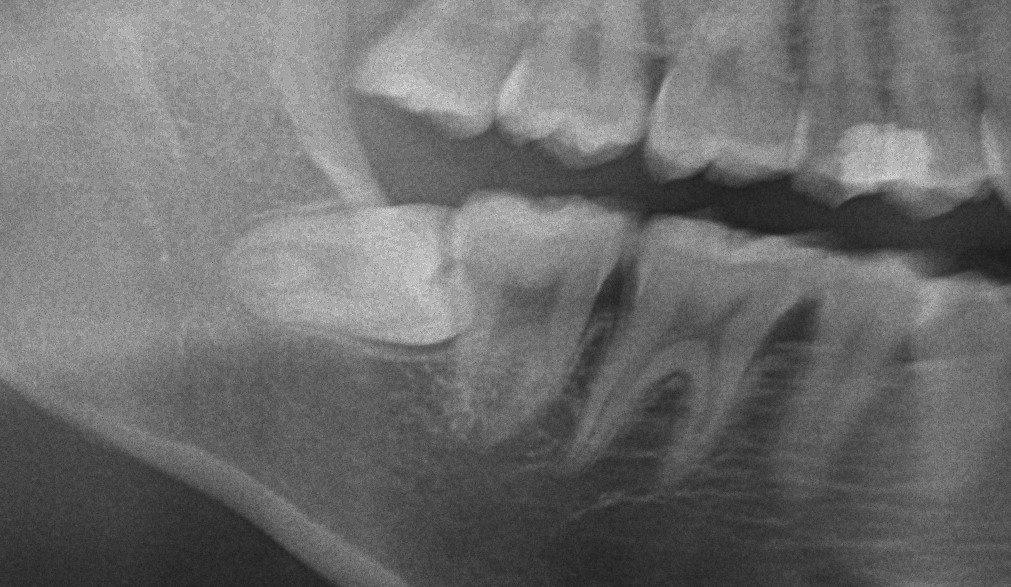

【動画解説】右下親知らずを抜きたい

今回右下親知らずを抜きたいということで来院された患者様です。 動画をとってみたのでどんな感じで親知らずが抜歯されていくのか?を見るいい機会になるのではないかと思いUPしました。 完全に埋まっている親知らずでも抜歯がうまい […]